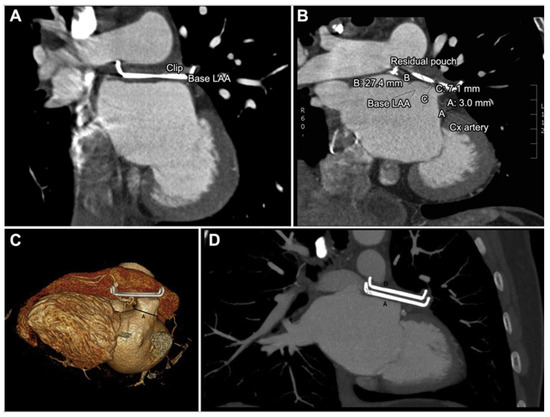

3.5. Epicardial Devices